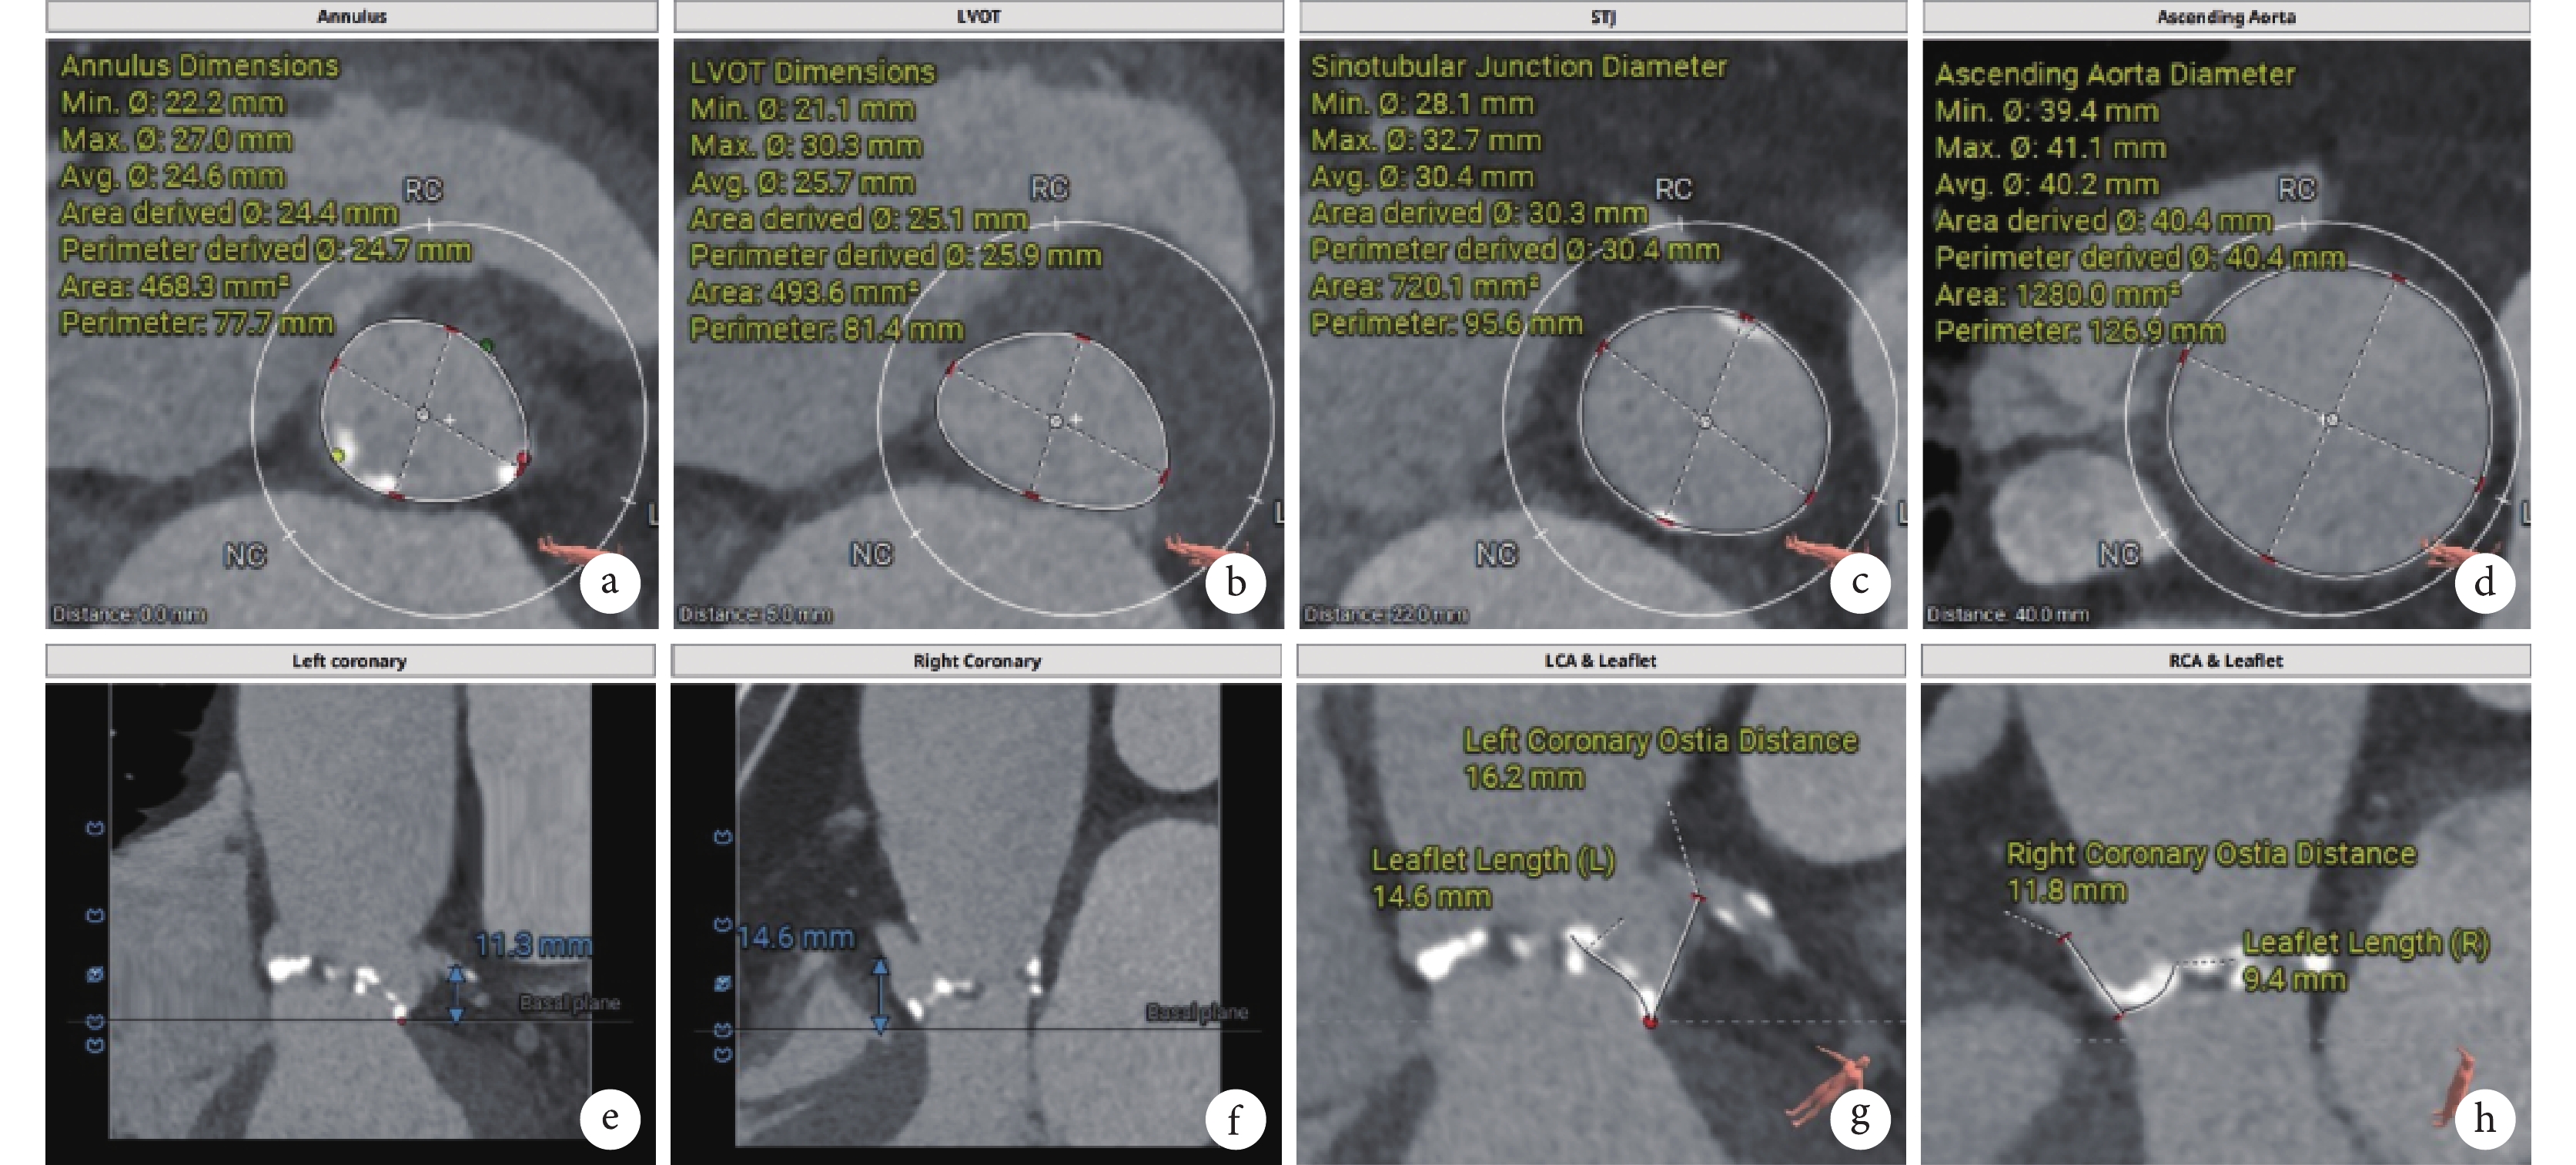

心臟超聲指標(主動脈瓣形態、功能及左心房左心室內徑)由超聲科醫生測量(Phillip CX50)。根據專家共識形成標準[4],術前及術后隨訪CTA數據用雙源CT掃描,并通過配備的AW3.0工作站進行分析(西門子)。以1 mm的層厚獲取圖像,后進行多周期重建,多平面觀察瓣膜錨定位置,模擬密封情況,結構鈣化的推擠程度的指標。隨訪CT檢查時采用相同掃描方案的回顧性門控,覆蓋心臟和升主動脈范圍,對無禁忌證的患者進行CTA檢查時采在收縮末期或舒張末期,觀察瓣膜植入深度,瓣葉活動情況的指標。在術前檢查和隨訪時均使用3mensio軟件對瓣膜植入深度、瓣膜支架偏心率等指標進行評估;見圖2。

a~b:瓣環、流出道測量;c~d:竇管交界、升主動脈測量;e~f:左冠高度、右冠高度;g~h:左右冠瓣葉長度、冠脈風險評測